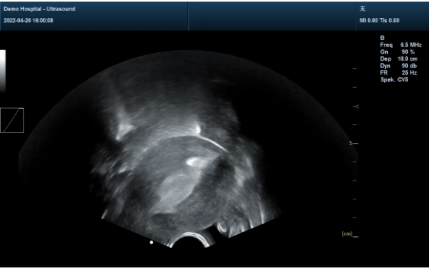

②全程超導(dǎo)可視:可視圖像顯影不受血污影響,操作方便,無(wú)菌安全,定位準(zhǔn)確,避免術(shù)中探測(cè)不到位、子宮穿孔、術(shù)后殘留等,是安全,精準(zhǔn),便捷的保障。